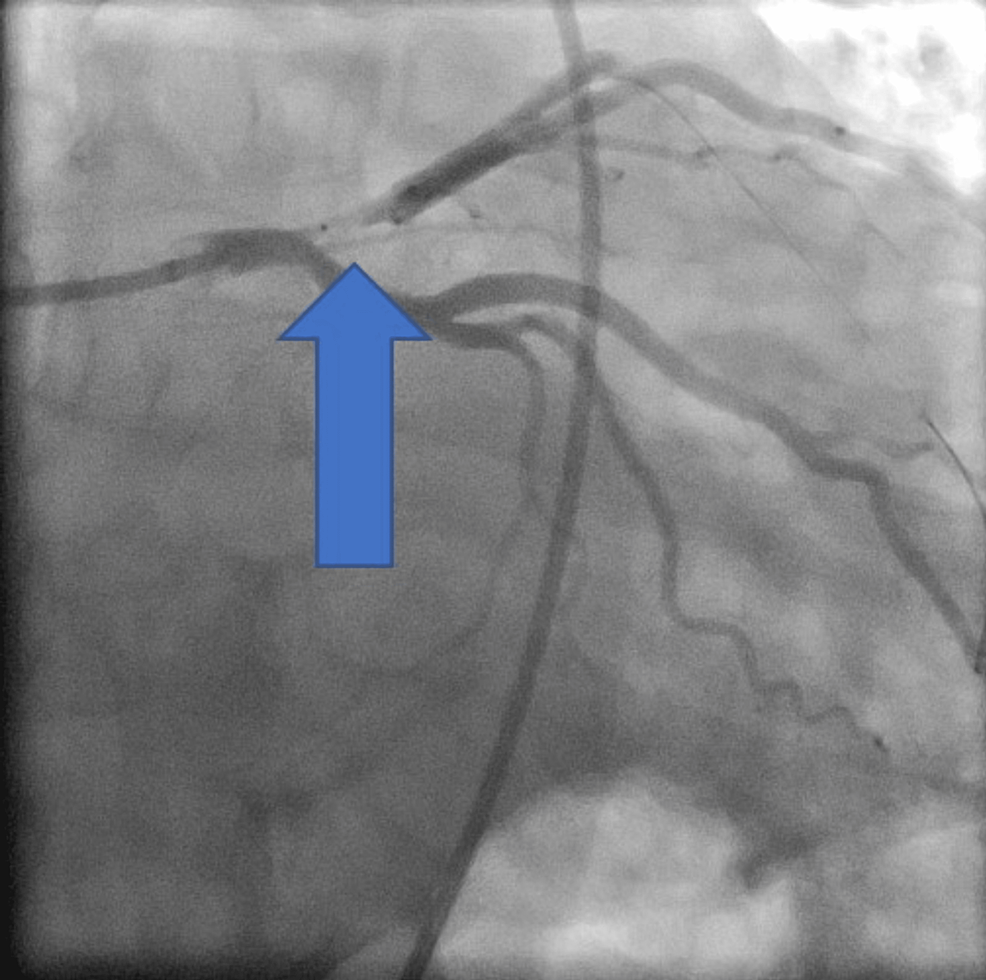

Coronary angiography showing subocclusive stenosis of the LAD (arrow How Is Lad Blockage Diagnosed It’s also sometimes referred to. A widowmaker is when you get a big blockage at the beginning of the left main artery or the lad. A heart attack involving the lad is typically more serious than other heart attacks. Usually a blockage of the lad artery has to be more than 70% to cause significant problems. A widowmaker heart attack. How Is Lad Blockage Diagnosed.